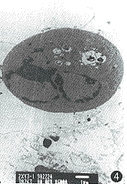

3. 1 μg/ml TRAIL作用于培养SMMC7721细胞8 h。电镜观察到细胞凋亡的形态学特征,细胞染色体固缩致密化,边缘化,出现凋亡小体,细胞膜保持完整(图3,4)。作用12 h后FACS分析观察到其明显的诱导凋亡活性(图5)。

图4 可溶性TRAIL,细胞染色体固缩致密化,边缘化,出现凋亡小体,细胞膜保持完整 ×6 000